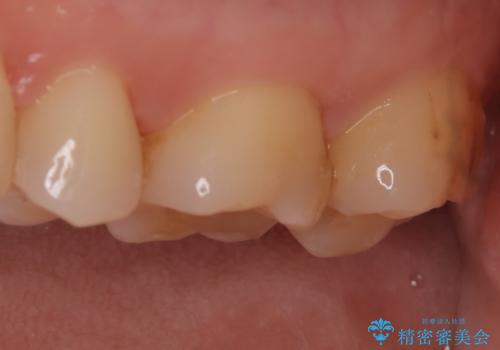

【セラミックインレー】適合の良いセラミックインレーを入れたい。

- 毎回フロスが引っかかることを気にされており、改善のため適合の良いセラミックインレーで修復しました。

以前に他院で詰め物をいれた時は、フロスが毎回ちぎれて大変だったそうですが改善して喜んでおられました。

当院のセラミックインレーは必ずラバーダムを使用して接着しています。